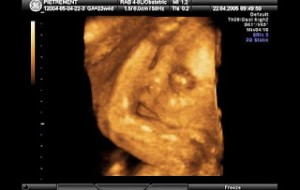

Hamileliğin (Gebeliğin) 35. Haftası Resim ve Video;

Bebeğin Boyutu: 43.7 cm, 1.9 kg